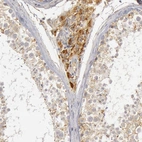

Immunohistochemical staining of human kidney shows strong cytoplasmic positivity in cells in tubules.